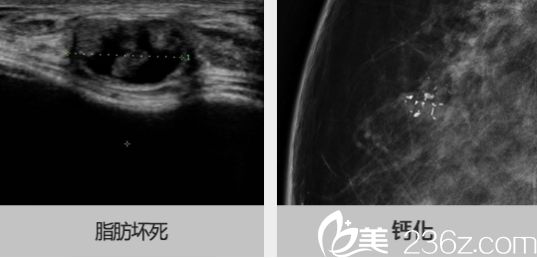

是从隆胸者身体腰、腹、臀、腿等脂肪较丰厚的部位抽取多余脂肪,经活化处理成纯净脂肪颗粒后,使用微型管针分条理均匀注入隆乳区使之成,达成有效隆胸的目的。它的填充材料完全来自于求美者自身,对人体无毒无害无刺激,人体本身也不会对注入的自身脂肪组织产生免疫、排异反应,安全性非常高。同时,将自体脂肪注入人体后,它并不会引起人体内分泌环境的改变,对乳腺本身不会产生伤害,对今后的生育、哺乳,不会有不良影响,能够确保隆胸整形的高安全度。

自体脂肪丰胸的手术,出于受区部位张力的限制以及存活率的考量,一次手术的注射量大致在每侧300~400ml左右。术后脂肪存活量大约一般能够达到大约200~300ml左右,效果相对来说还是比较令人满意的。对于本身罩杯较小的女性,外形的改变是非常明显的,一般都能达到2~3个罩杯的提升。